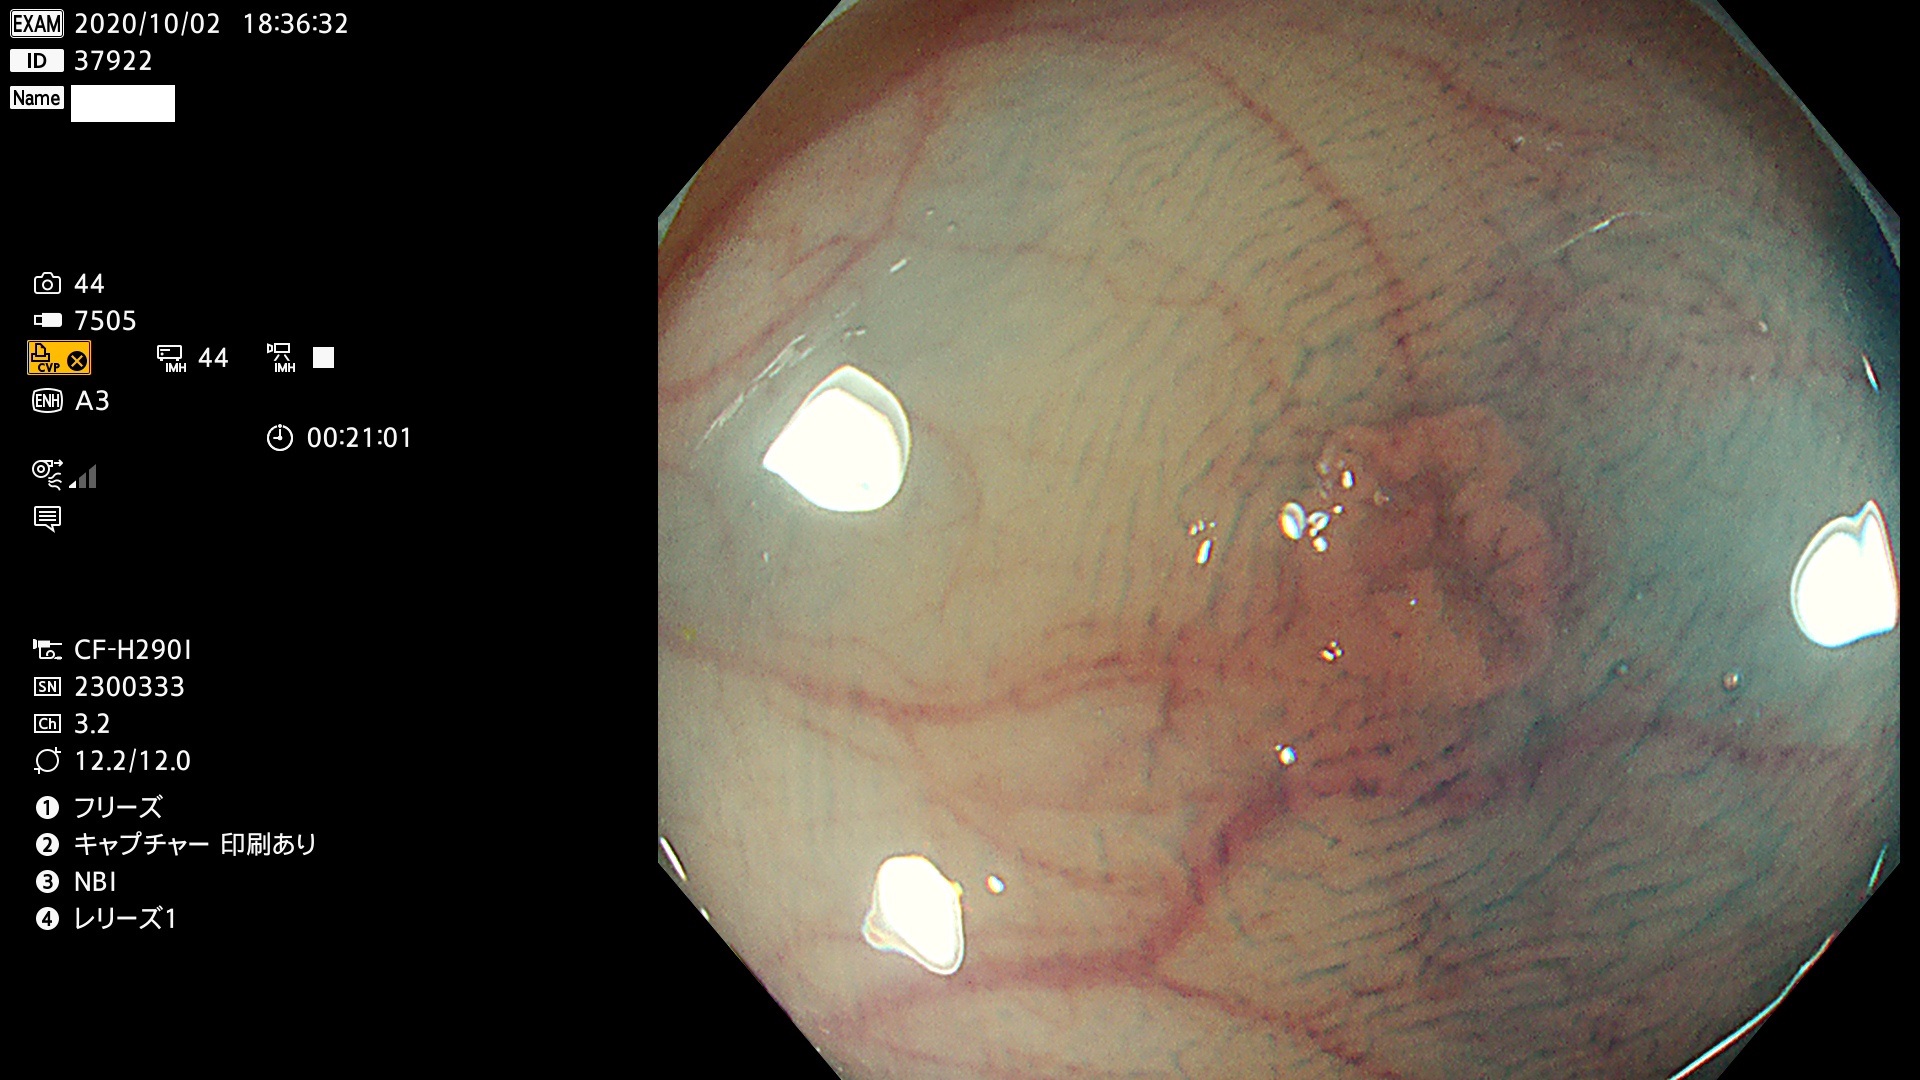

37900 37902 37903 37904 37905 37906 37907 37909 37910 37911 37912 37913 37914 37915 37916 37917 37919 37921 37922 37923 37926 37928 37929 37930 37931 37933 37934 37935 37936 37937 37938(SSAPのみ) 37939 37940 37941 37942 37943 37946 37947 37948 37949 37951 37952 37953(SSAPのみ) 37955 37956 37957(SSAPのみ) 37958(SSAPのみ) 37960 37962 37963 37964 37966 37967 37968 37971 37972 37973 37975 37976 37977 37979 37982 37983 37984 37985 37986 37987 37988 37989 37990 37991 37992 37993 37994 37995 37996 37998 37999

発見困難で危険性の高い平坦型病変(上記100名より抽出)